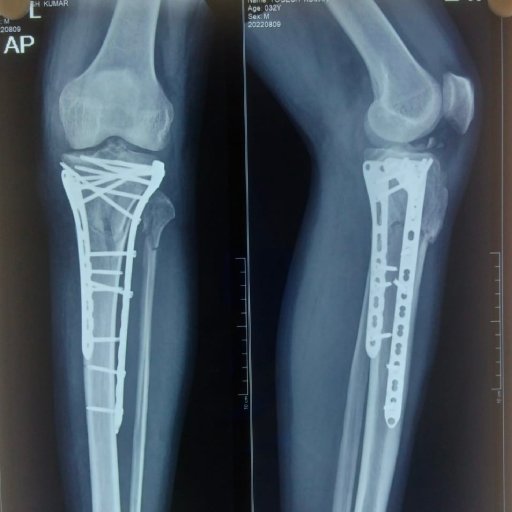

Knee preservation involves the use of non-surgical or surgical methods to maintain the integrity of a deteriorating joint. Its goal is to delay or prevent the need for joint replacement surgery, thus preserving natural joint function and mobility.